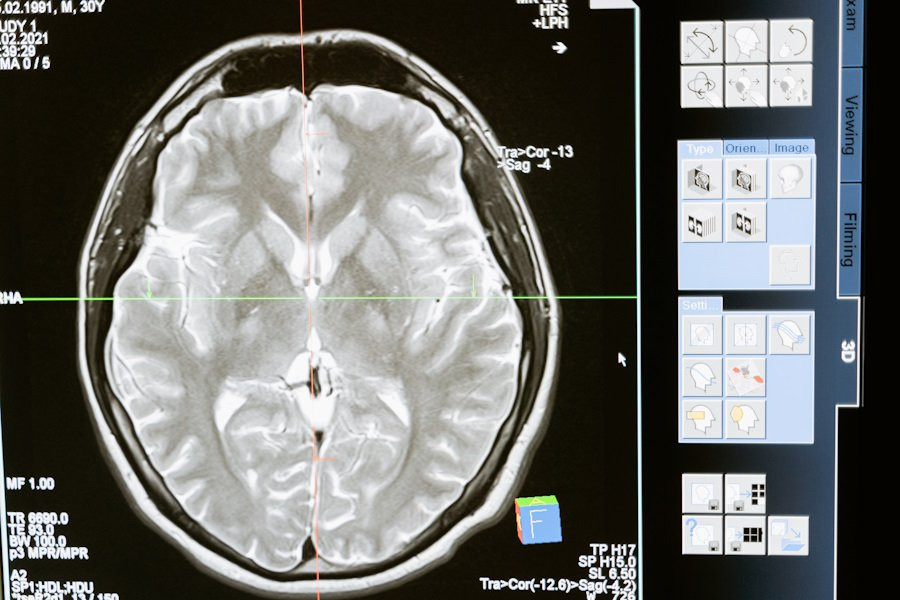

В исследовании психологов University of North Carolina была протестирована новая замкнутая система для измерения и стимулирования электрических паттернов мозга у пациентов с тяжелым депрессивным расстройством. Результаты показали значительное улучшение симптомов у большинства участников, сообщает Medical Xpress.

Наш мозг активно генерирует электрические сигналы в различных ситуациях, будь то физическая активность, еда или отдых. В состоянии покоя, когда мы думаем или просто расслабляемся, преобладают альфа-колебания на частоте 8–12 Гц. У пациентов с депрессией часто наблюдается нарушение равновесия этих альфа-волны в префронтальной коре, особенно в левой части.

Для решения этой проблемы учёные разработали замкнутую систему, способную измерять индивидуальные альфа-частоты и стимулировать мозг слабым переменным электрическим током. Этот метод направлен на восстановление нормального баланса альфа-колебаний.